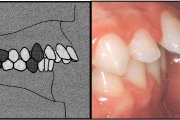

) Röntgenülesvõte. Ülemise esimese jäävmolaari lõikumine on takistatud 2. piimamolaari tõttu

Esimese jäävmolaari ektoopiline lõikumine